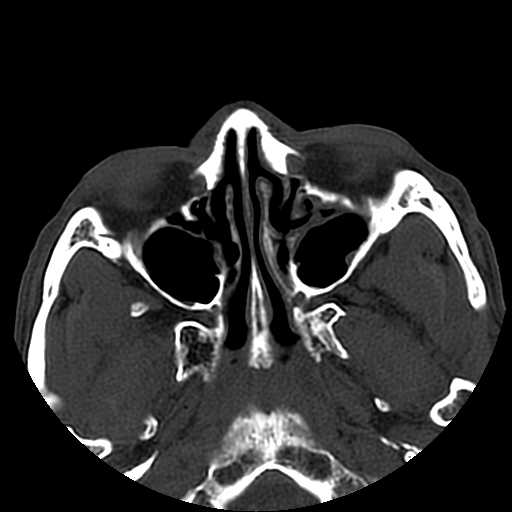

以下是引用liaoqiang在2008-7-16 21:15:00的发言:[br]右侧鼻骨骨折

以下是引用zxd95在2008-7-16 21:39:00的发言:[br]右侧上颌骨额突骨折。[br][br][br][br]